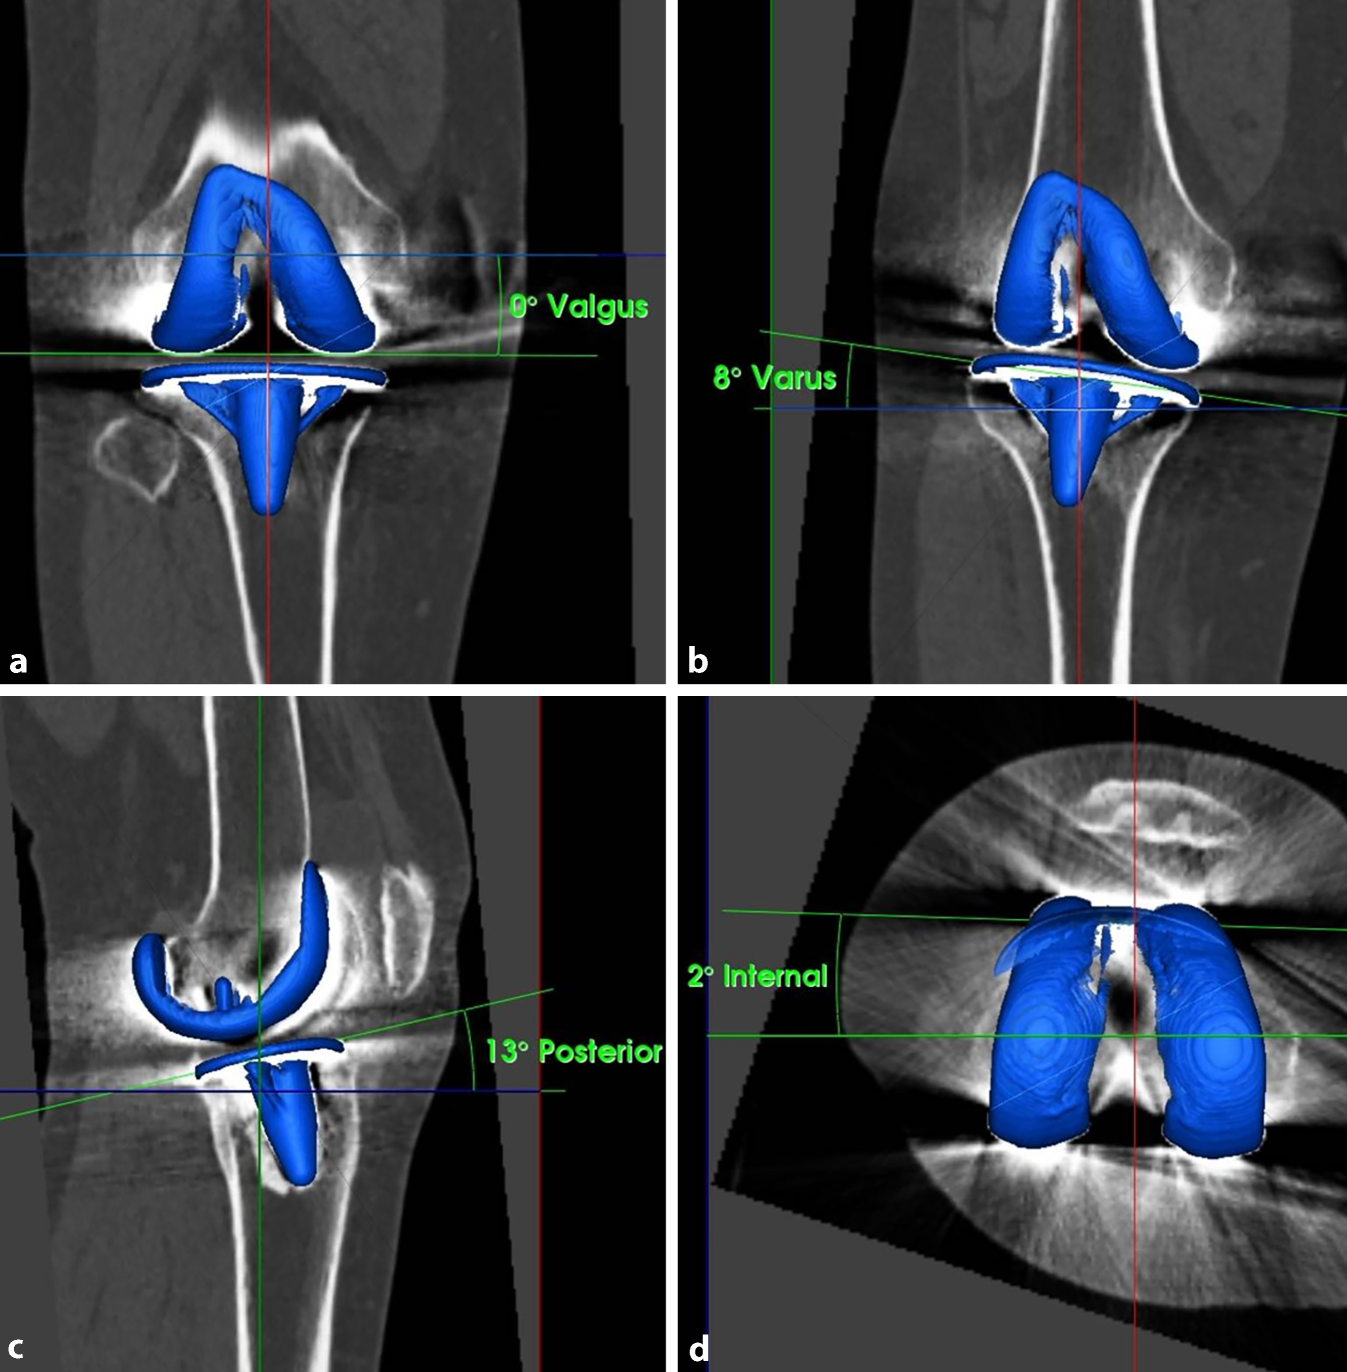

CT-Aufnahmen bieten eine präzisere dreidimensionale Darstellung und liefern genauere Informationen über die Lageverhältnisse der Implantate. Mit einer Spezialsoftware lässt sich die Position der Knieprothesenkomponenten exakt ausmessen (Abb. 4). Dies ist unabdingbar, um eine mechanisch bedingte Ursache der Gelenksteife beurteilen zu können. Auch das Ausmaß und die Größe von Osteolysen und Lockerungssäumen kann man in der CT sensitiver und verlässlicher erkennen als in der Röntgenaufnahme.

Abb. 4

3D-Vermessung einer Knieprothese a koronar (femoral varus-valgus), b koronar (tibial varus-valgus), c seitlich (tibialer Slope), d axial (femorale Rotation)